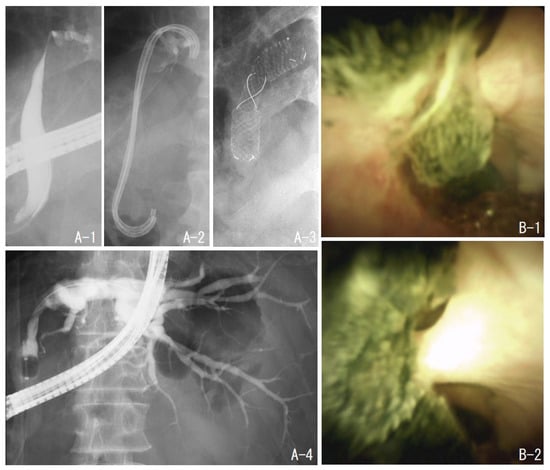

2.4. Case 2: Treatment with a Metal Stent to Expand Stenosis in a Patient after Right Hepatectomy

2.5. Case 3: EHL under POCS with Colonoscopy with Postoperative Anatomy